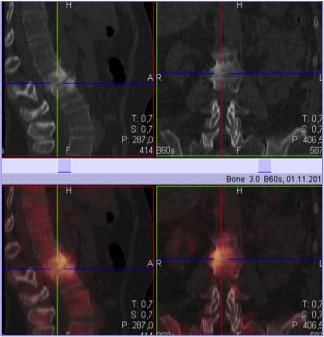

Types of tests: planar bone scintigraphy, SPECT/CT of the skeleton.

Aim: to visualize abnormalities of the skeleton (local areas of metabolic dysfunction of bone tissue).

Nuances: bone scintigraphy is a high-sensitivity / low specificity test. In some instances, osteochondrosis, arthrosis and changes of the skeleton caused by trauma may lead to an erroneous conclusion. In this case, it is recommended to perform SPECT/CT. The use of Tc-99m-labeled bisphosphonates increases the sensitivity of the test.

SPECT/CT of the skeleton allows a better assessment of the condition of the skeleton if the results of bone scintigraphy are inconclusive. It helps to identify metastases that are 5-10 mm in size. It is a reliable technique for evaluating the efficacy of treatment of metastases with bisphosphonates and chemotherapeutic agents. SPECT/CT is recommended for patients with primary cancer of the prostate and breast, kidney and urinary bladder cancer, lung cancer (if PET/CT cannot be performed), melanoma, histiocytosis, malignant neoplasms of the gastrointestinal tract and reproductive system, embryonal tumor and osteosarcoma.